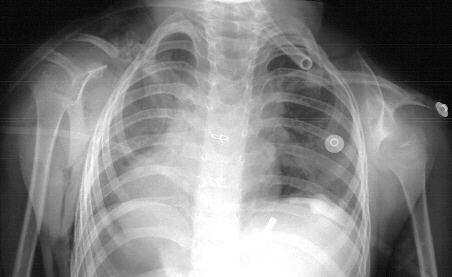

HISTORY: This is a 5 + 3 year old white female the product of a full-term

normal spontaneous vaginal delivery with a diagnosis of CHARGE syndrome

(defects of the eyes, ears, heart, choanal atresia, mental retardation,

and genital hypoplasia) who presented for evaluation of a webbed neck left

side worse than right. Pt has developmental delay and began walking at

4 years of age. She had undergone previous surgery for strabismus and atrial

septal defect.

PHYSICAL EXAM: General - Small for chronological age

- HEENT - Defects of the eyes and ears noted

- NECK - Shortened and Webbed left worse than right

- BACK and SHOULDER - elevated scapula left worse than right , scapula

rotated down and away from spine, shoulder abduction 110 degrees on right

and 100 degrees on left

- Cavendish Grade - right II, left III

XRAYS: Demonstrate elevated left scapula worse than right,

No evidence of omovertebral bone on either side, Thoracic Kyphosis - no

other spinal abnormalities